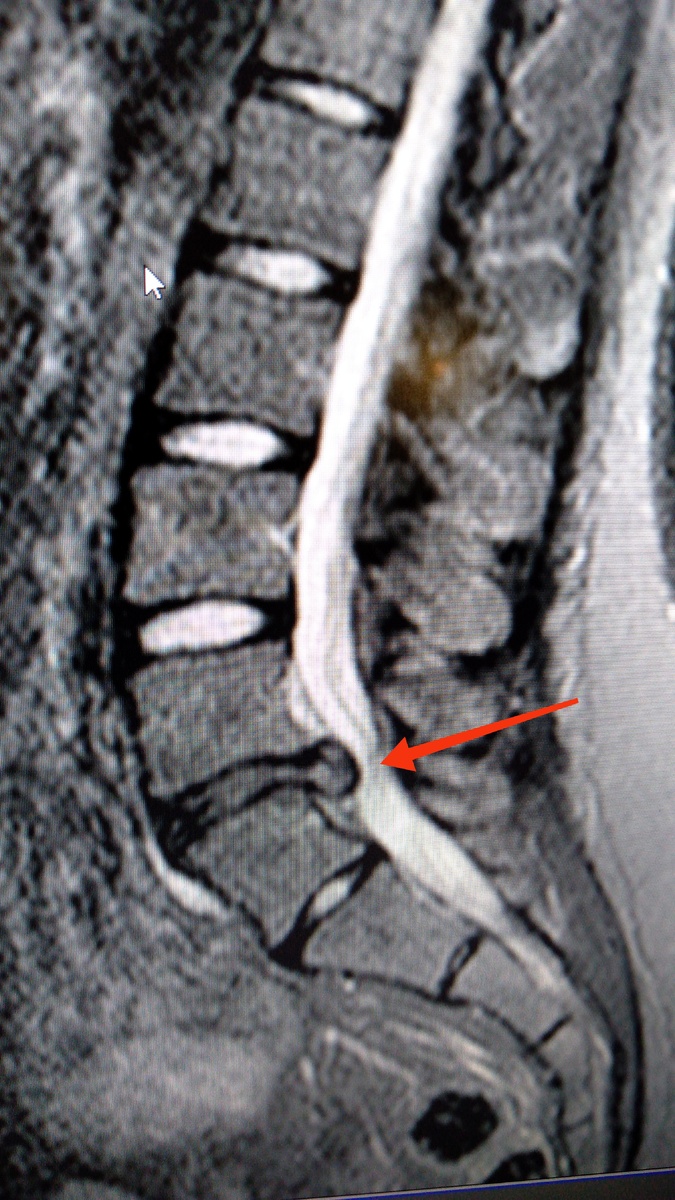

· Протрузиям и грыжам: увеличенное давление на фиброзное кольцо может привести к его растяжению и разрыву, в результате чего пульпозное ядро выпячивается (протрузия) или вытекает (грыжа), сдавливая нервные корешки и вызывая боль, онемение, слабость в ногах (ишиас).

Фото из личного архива

· Стеноз позвоночного канала: ожирение увеличивает риск развития дегенеративного стеноза – сужения канала, в котором проходит спинной мозг, из-за разрастания костных структур и утолщения связок.